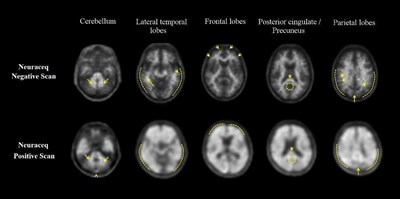

Interpretation of the images is made by visually comparing the activity in cortical gray matter with activity in adjacent white matter. Regions displayed in the PET images which ‘anatomically’ correspond to white matter structures (e.g., the cerebellar white matter or the splenium) should be identified to help the readers orient themselves. Images should be viewed and assessed in a systematic manner, starting with the cerebellum and scrolling up through the lateral temporal and frontal lobes, the posterior cingulate cortex/precuneus, and the parietal lobes. For a gray matter cortical region to be assessed as showing ‘tracer uptake’, the majority of slices from the respective region must be affected.

For each patient, the PET image assessment is categorized as either “β-amyloid-positive” or “β-amyloid-negative”. This determination is based on the assessment of tracer uptake in the gray matter of the following four brain regions: the temporal lobes, the frontal lobes, the posterior cingulate cortex/precuneus, and the parietal lobes; according to the following ‘rules for assessment’ [see Warnings and Precautions (5.1)]:

- β-amyloid negative - tracer uptake (i.e., signal intensity) in gray matter is lower than in white matter in all four brain regions (no β-amyloid deposition)

- β-amyloid positive - smaller area(s) of tracer uptake equal to or higher than that present in white matter extending beyond the white matter rim to the outer cortical margin involving the majority of the slices within at least one of the four brain regions (“moderate” β-amyloid deposition), or a large confluent area of tracer uptake equal to or higher than that present in white matter extending beyond the white matter rim to the outer cortical margin and involving the entire region including the majority of slices within at least one of the four brain regions (“pronounced” β-amyloid deposition). There is no known clinical or histopathologic correlation distinguishing “moderate” from “pronounced” β-amyloid deposition.

Examples of positive and negative scans for each of the four brain regions are illustrated in Figure 1.

Figure 1 Axial view of negative (top row) and positive (bottom row) Neuraceq PET scans

Cerebellum: A contrast between the white matter (arrows) and gray matter is seen in both negative and positive scans. Extracerebral tracer uptake in scalp and in the posterior sagittal sinus (arrowhead) can be seen. Lateral temporal lobes: Spiculated or “mountainous” appearance of the white matter (arrows) is seen in the negative scan, and radioactive signal does not reach the outer rim of the brain (dashed line) due to lower tracer uptake in the gray matter. The positive scan shows a “plumped”, smooth appearance of the outer border of the brain parenchyma (dashed line) due to tracer uptake in the gray matter. Frontal Lobes: Spiculated appearance of the white matter in the frontal lobes (arrows) is seen in the negative scan. The positive scan shows the tracer uptake in these regions has a “plumped”, smooth appearance due to the increased gray matter signal (dashed line). Posterior cingulate/precuneus: Adjacent and posterior to the splenium (arrow), these regions appear as a hypo-intense “hole” (circle) in the negative scan, whereas this hole is “filled-up” (circle) in the positive scan. Parietal lobes: In the negative scan, the midline between the parietal lobes can be easily identified (long arrow); white matter has a spiculated appearance (short arrow) with low signal near the outer rim of the brain (dashed line). In the positive scan, the midline between the parietal lobes is much thinner. The cortical areas are “filled-up” and are smooth in appearance as tracer uptake extends to the outer rim of the brain.